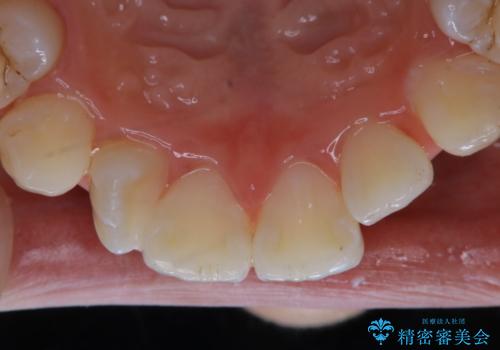

矯正中のPMTC60分コース

- インビザラインでの矯正治療中の方です。全体的に黄ばみ・黒ずみが気になるとのことでした。

PMTC60分コースを行いました。

PMTC(保険外治療)は、毎日の歯磨きで落としきれない汚れや、コーヒ、紅茶・タバコのヤニなどの着色も除去します。目には見えない歯と歯の間・歯肉の境目・インビザライン中はアタッチメント周囲などに残っているプラーク(歯垢)もしっかり取り除きます。PMTCでは専門的な機械や材料を使用して、徹底的に汚れを除去するため、虫歯・歯周病・口臭予防などにつながります。

またPMTCを行うことで、ご自身本来の歯の色になり自然な明るさになります。